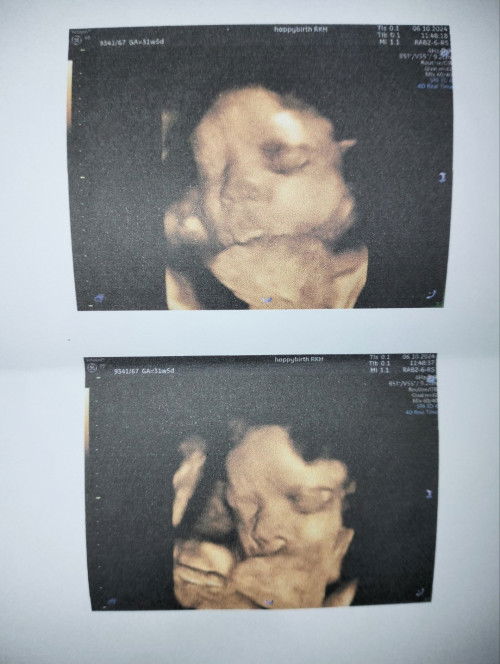

อายุครรภ์ 31+5w น้ำหนักลูก 1,834 กรัม น้อยไปไหมคะแม่ๆ คุณหมอบอกให้เพิ่มน้ำหนักลูกค่ะ มีวิธีการทานบำรุงเพิ่มเติมบ้างไหมคะ🥹#ขอคำแนะนำกับแม่ๆด้วยนะคะ